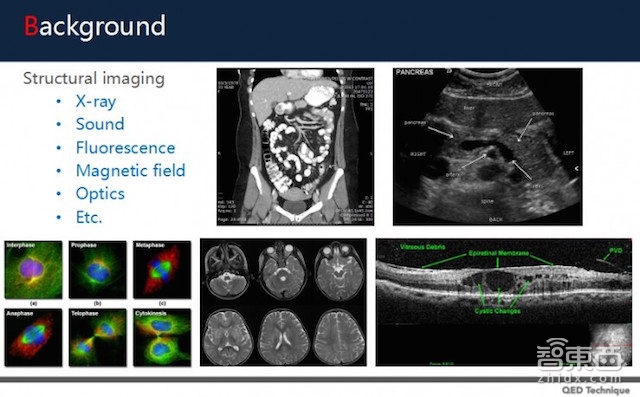

虽说以上都归类为医疗影像,但医疗影像也有细分范畴。目前医疗影像可以分成结构性影像(Structural Imaging)和功能性影像(Functional Imaging):

结构型影像:包括X光、CT、MRI核磁共振成像等能够看清人体器官组织结构的医疗影像,通常用于检测癌症/结节这类机体存在物理性状改变的病症;

(图片来自雅森科技高级算法研究员杨士霆)

功能性影像:包括呈现脑部电流改变的脑波图、基于功能磁共振成像(Bold-fMRI)检测血氧水平等,依据器官新陈代谢情况、性状变化等做出诊断的医疗图像。

相比功能性影像,结构性影像的空间解析度更好,更适合人工智能在其中进行落地。目前,大多数进军AI医疗影像的公司主打的都是结构性影像的识别诊断,比如上文提到的医拍智能、腾讯“觅影”、万里云&阿里健康“Doctor You”平台、迪英加科技、推想科技、图玛深维等等。